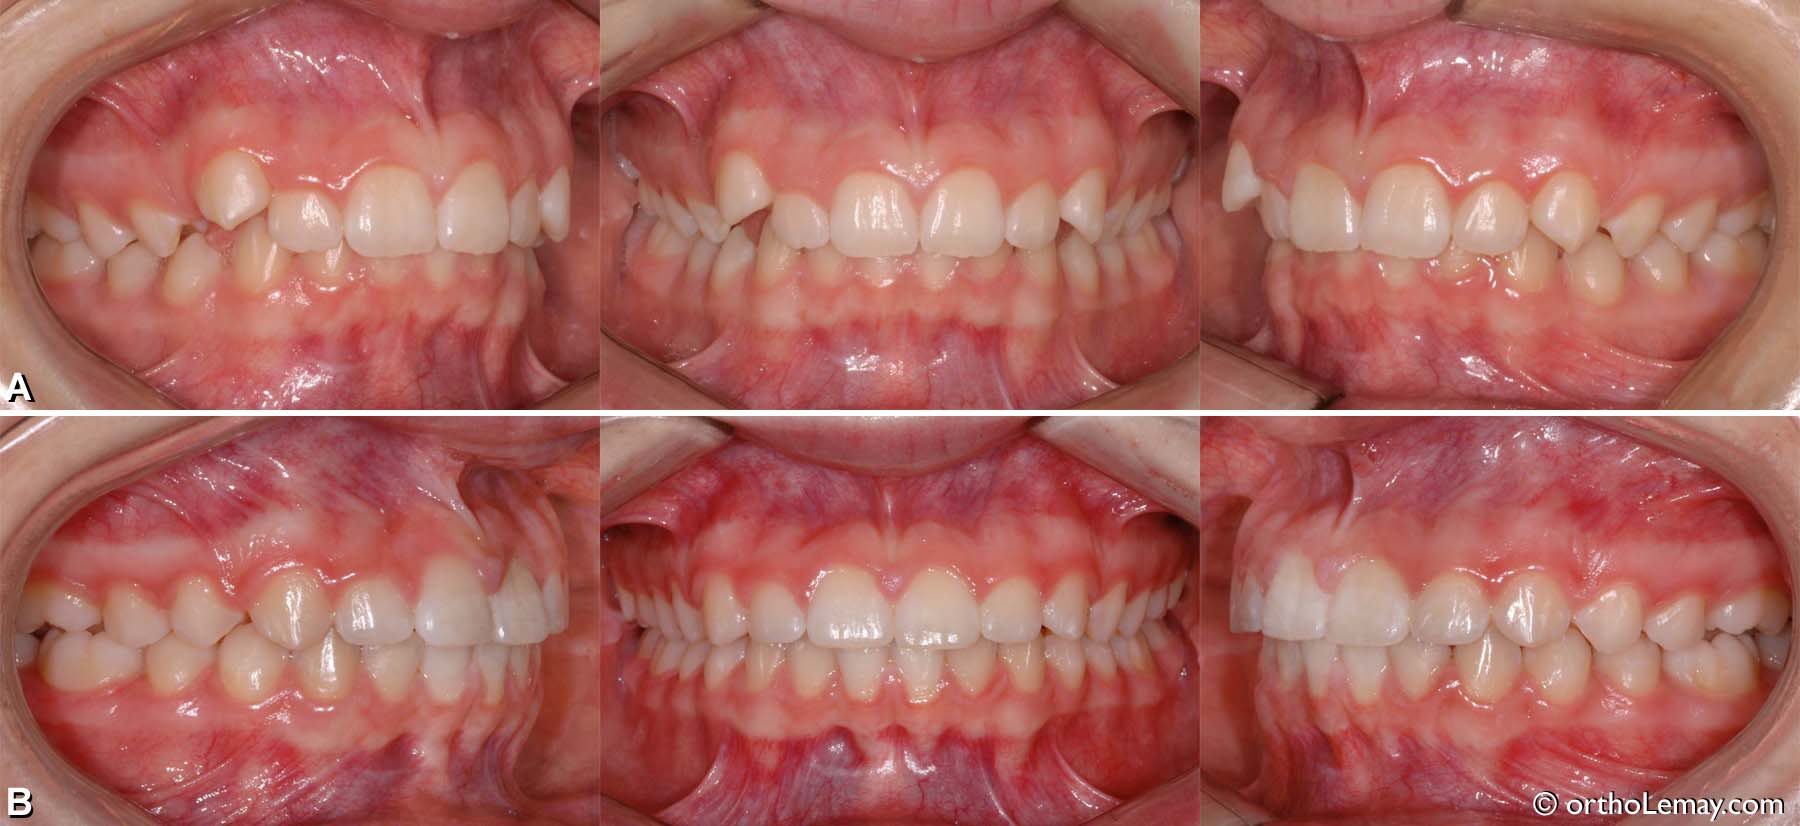

Exemple de traitement de malocclusion classe 1 (13)

(A) Jeune femme de 21 ans avec encombrement dentaire modéré et arcades étroites.

(B) Après le traitement d’orthodontie, expansion et alignement sans extractions.